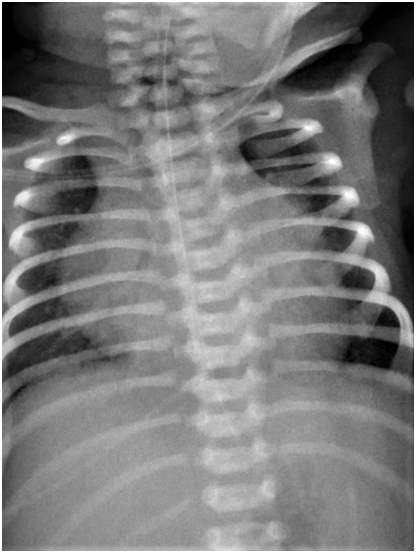

A late preterm 36weeks gestation female infant was delivered by caesarian section to a P3+0 32-year old woman with an uneventful pregnancy, except for fetal bradycardia with ventricular rate of 57bpm on antenatal scan. Fetal echocardiography before birth confirmed the diagnosis of CCHB and normal cardiac anatomy. The mother was completely asymptomatic; however, screening for possible maternal autoimmune diseases was done based on the antenatal scan. Maternal anti-extractable nuclear antigen (ENA) profiles, including the levels of anti-ribosomal P (Rib-P-protein), anti-smooth muscle, anti-Smith (for SLE), anti-ScL-70 (anti-topoisomerase for scleroderma), and ENA Jo-1(for dermatomyositis) antibodies were less than 0.1 U (negative<0.7 U). Only the anti-Ro/SSA antibody level was 5.78U (positive>1U), while the anti-La/SSB antibody level was 0.137U (negative). The Apgar score was 5 and 9 at 1 and 5min, respectively, and only T-piece resuscitator support was needed for labored breathing. On examination, the birth weight was 2.775 (50th centile); head circumference, 35 cm (50th centile); and length, 50 cm (50th centile). The infant was maintaining saturation on nasal continuous positive airway pressure support with acceptable blood gases; no dysmorphic features and no skin stigmata were observed. Chest examination showed mild subcostal recessions with respiratory rate of 40 -50/min. Heart rate ranged from 60 to 65bpm with grade II systolic murmur over the left upper parasternal border. Femoral pulses were palpable with mean blood pressure of 50-55mmHg in both upper and lower limbs. The liver was palpable about 3 cm below the right costal margin but not tender. The spleen was also enlarged 2-3cm below the left costal margin. Chest X-ray on admission revealed mild cardiomegaly with plethoric well- inflated lung fields (Figure 1). The patient was reviewed by the pediatric cardiology team, and the ECG indicated CCHB with complete PR dissociation (P-P rate 150bpm and R-R rate 57bpm) (Figure 2). Echocardiography showed small PDA, LA/Ao 1.0, functional MR, functional TR, and mild pulmonary hypertension, with dilated right heart.

Figure 1 Chest radiogram on admission shows mild cardiomegaly and plethoric lung fields.